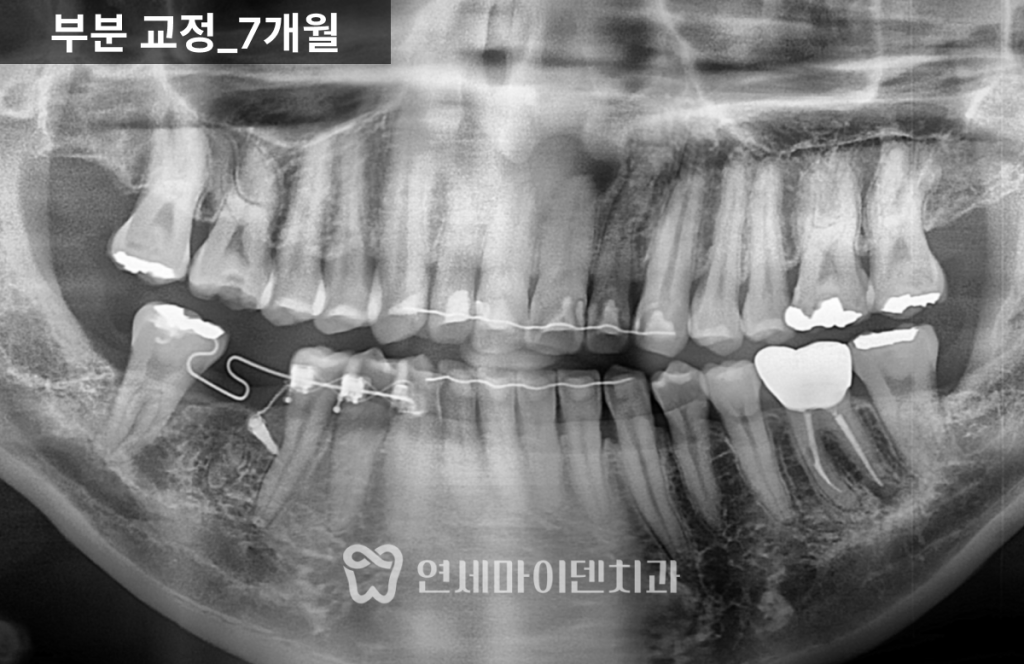

정밀한 힘 조절이 필요합니다.치아교정 7개월차: 공간 확보

약 7개월이 지나면서

쓰러졌던 7번 치아는 눈에 띄게 세워졌고

임플란트가 들어갈 수 있는 공간이

충분히 확보되었습니다.물론 더 이상적인 위치까지

완벽하게 이동시키는 것도 가능했지만,치아 뿌리 이동 범위와

치료 기간을 고려해

교합에 무리가 없는 선에서

효율적으로 마무리하는 전략을 선택했습니다.

목표로 해야 합니다.임플란트 식립과 마무리

공간 확보 후

임플란트를 정확한 위치에 식립했습니다.임플란트가 뼈와 안정적으로 결합되는 동안

교정을 병행해 공간을 유지했고,최종적으로 교합 간섭 없이

자연스러운 씹는 기능을 회복했습니다.

교정 전과 비교하면

임플란트 공간은 체감상 두 배 이상 확보되었고

다른 치아들의 불필요한 이동 없이

치료가 안정적으로 종료되었습니다.협진이 중요한 이유